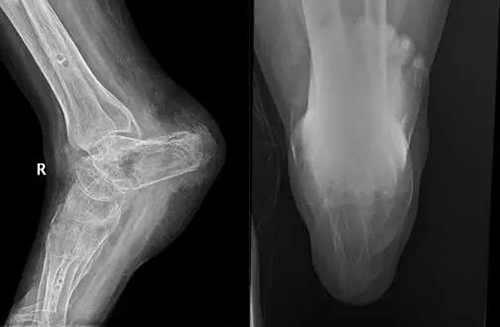

于是王主任进行了细致的测量研究,术前设计了完美的手术方案。于2017-07-04在全麻下对其进行了Ilizarov外固定架固定+右距骨截骨延长跟骨再造术。术后定期换药,刀口愈合良好,在术后一周,开始进行延长。每天延长多少毫米,每天改变多少度,王主任都进行了详细的计算,并对患者进行了细心的指导。患者熟练掌握了延长方式及步骤后出院。

安装Ilizarov外固定架,将距骨延长,进行跟骨再造

时间就在不断的复查、拍片、纠正角度的过程中悄悄流逝。不知不觉,1年过去了。

跟骨又“长”出来了!!!

部分跟骨缺损,可以通过腓骨移植、髂骨移植等手术进行修复重建,此类手术需要其他部位取骨,创伤大,容易造成供区疼痛,功能障碍。但是对于跟骨完全缺失的患者,骨移植手术往往不能解决问题。而通过Ilizarov骨延长再生技术,可以很好的解决这个问题,使缺失的跟骨重新长出来。